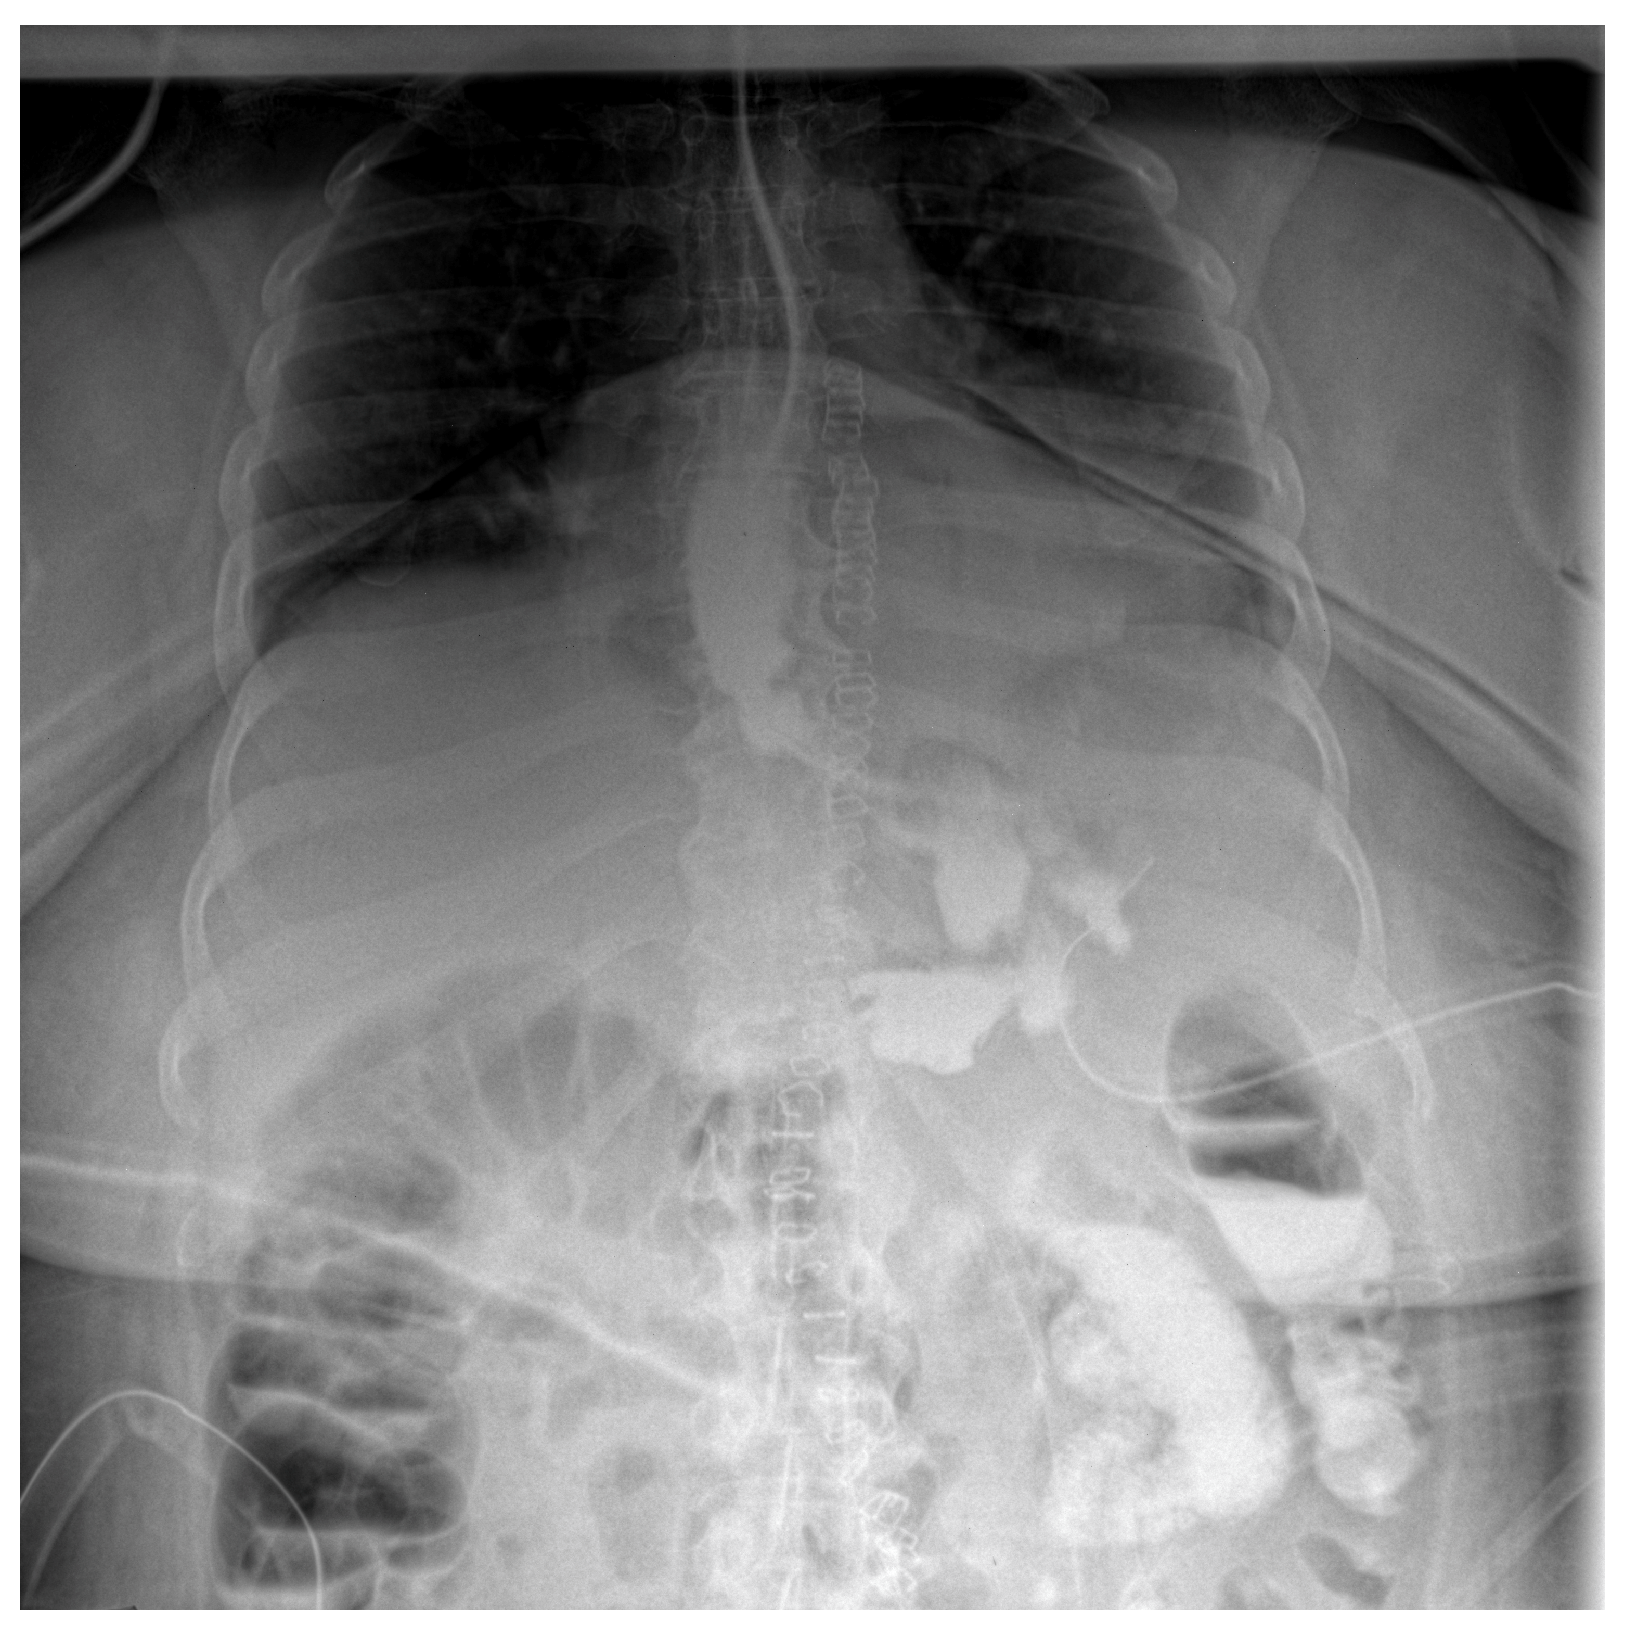

Follow-up staged procedures were performed at 6–7-day intervals, consisting of endoscopic replacement of the E-VAC system at the fistula site, with continuous monitoring of its evolution through direct endoscopic assessment. After six consecutive exchanges of the double-lumen endoluminal vacuum system, endoscopic evaluation confirmed complete closure of the fistulous tract, allowing the gradual reintroduction of oral intake (only liquid form). Under close supervision, the patient tolerated oral feeding for one week, with serial contrast studies using iopamidol confirming the absence of residual fistulous communication (Figure 3).

Figure 3.

Contrast abdominal radiography—with E-VAC in place without leakage of the contrast substance.